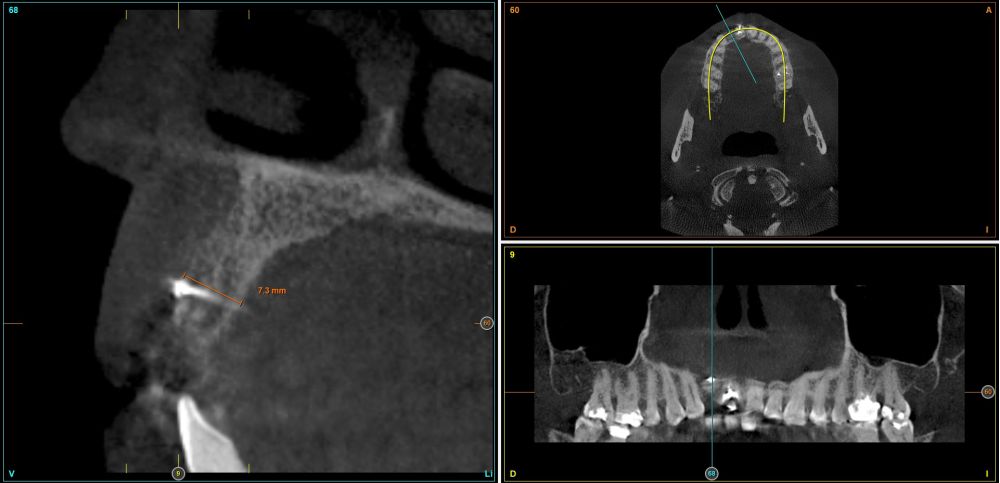

To continue with the study of the case, a Cone Beam is performed where we can observe three-dimensionally the position of the implant located in position 1.2. In the sectional cuts it is visualized completely positioned toward vestibular with an almost complete resorption of the cortical bone of this area, which explains the underlying soft tissue problems. The periapical radiography shows the position of the implant with respect to adjacent teeth (Figures 5 and 6). With this image we proceed to create a flap and the explantation of the implant. The crown located in tooth 1.1 is also removed to be able to make another crown that will serve to support the provisional extension for zone 1.2, while the first procedure heals. In this first approach a block grafting obtained from the mandibular ramus is also placed which is fixed with a microscrew in the area to be regenerated where the vestibular cortical has been lost. Once fixed and positioned, it is filled around the block grafting with particulate bone obtained with a bone-scraper of the same donor zone embedded in PRGF-Endoret for better fixation and cellular viability (Figures 7-9).

Four months later, a new dental cone-beam is performed to quantify the gain obtained in width with the regenerative procedure. It is observed in the sectional cut that a crest width of more than 7 mm and a complete regeneration of the alveolar ridge has been achieved, allowing the insertion of a new dental implant in the adequate position (Figure 10). In the surgical reentry, the information of the Cone-Beam is verified with a total integration of the graft material, as shown in the clinical images at the time of lifting the flap for the insertion of the implant (Figures 11 and 12). The microscrew is removed and the implant is placed, which is performed by vestibular compression of the graft to gain in this manner even more contour in this area (Figure 13). The implant is left in a surgical phase, with a low healing abutment that allows a subsequent location of the same without an aggressive soft tissue surgery when the construction of the prosthesis is initiated. The provisional crown remains as an extension from the tooth 1.1.